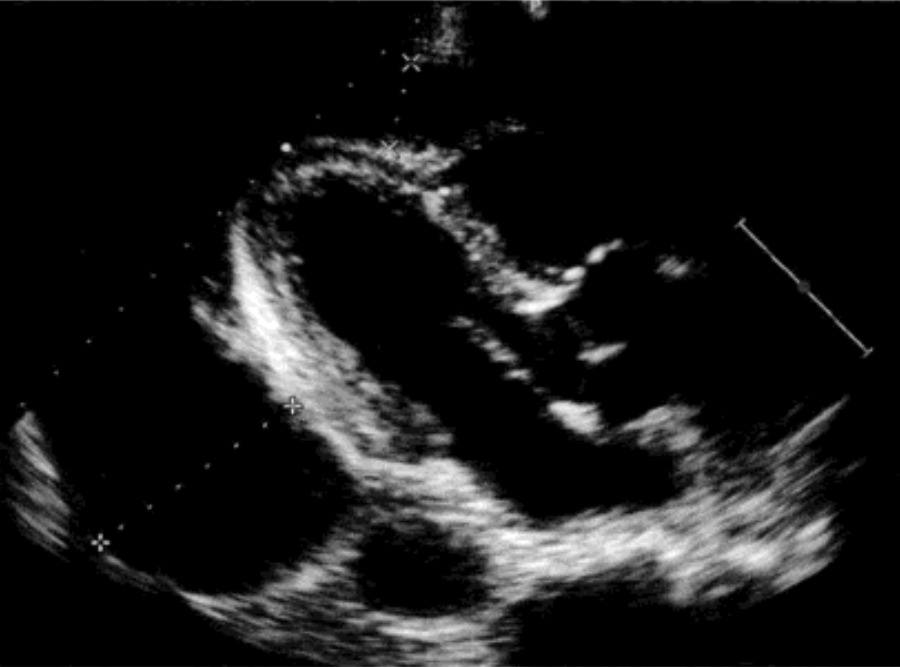

大量:左室后壁后方无回声区>2cm,液体量>500ml。右室前壁、室间隔及左室后壁呈同向运动,并出现由于心脏自由摆动而出现的摇摆运动。

心包积液也可以是包裹性的,在心脏手术、结核性心包炎、心脏外伤和胸部放疗后,心包的炎症性渗出使心包积液的分布不均匀。它可以发生在心包腔的任何部位,手术后最常见于左室或左室与左房的后方,因为前方是心包切开区,常有粘连;邻近右房的包裹性积液也常见。

心包积液时也可发现心包腔无回声区内有一些疏松的纤维样条状回声随心脏运动而漂动,有证据表明,这种少量的纤维样条带与以后发生心包缩窄并不相关。但是大量的纤维条带常见于化脓性心包炎和结核性心包炎,包裹在心脏的周围,有发生心包缩窄的倾向。一部分血性心包积液,心包腔内出现自显影现象,可能与红细胞聚集有关。